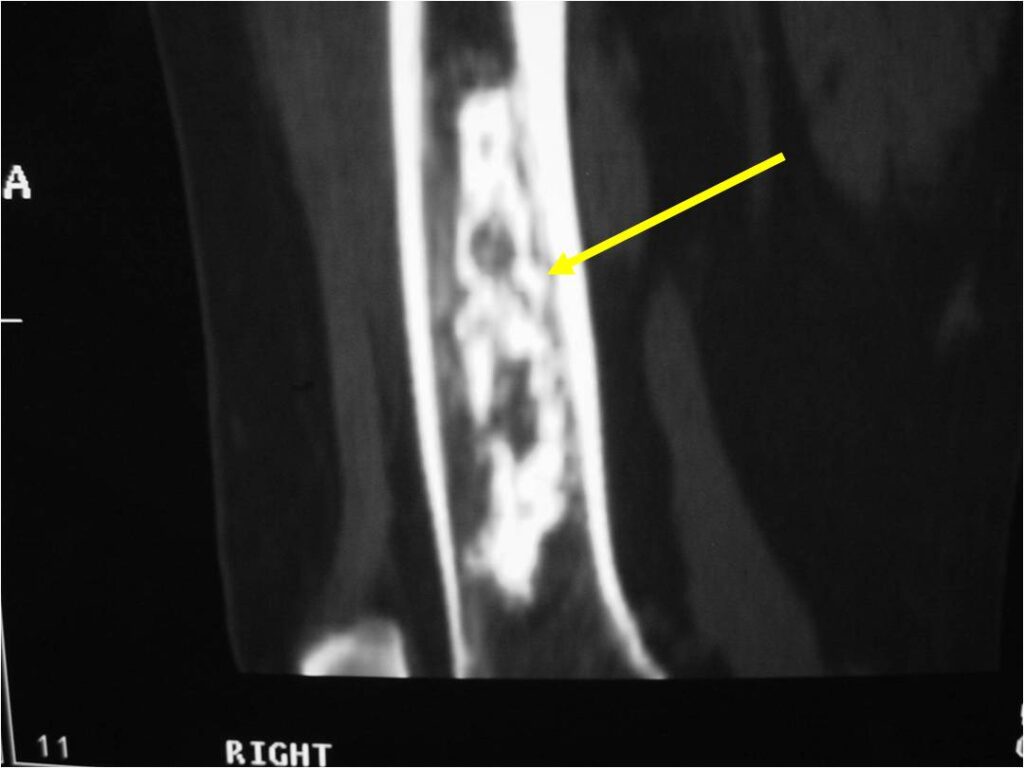

- MRI

- Lobulated margin

- Marked increased intensity long TR images

- Calcified chondroid – low intensity all sequences

MRI:

- Lobulated margin (Lobular Growth Pattern)

- T1 Weighted Images: Intermediate Signal Intensity

- Calcifications will be low signal

- T2 Weighted Images: High Signal Intensity

- High water content shows as high signal on T2 weighted images

- There should never be any cortical destruction nor a soft tissue component. If this exists then the tumor must be a chondrosarcoma.

- Endosteal scalloping and cortical expansion is acceptable for phalangeal tumors. In most benign long bone cartilage tumors there is minimal endosteal scalloping but there should be no cortical expansion nor thickening. There should be no cortical destruction and no soft tissue component associated with an enchondroma. Cortical destruction, periosteal thickening, cortical expansion and a soft tissue component indicates a chondrosarcoma of the long bone.